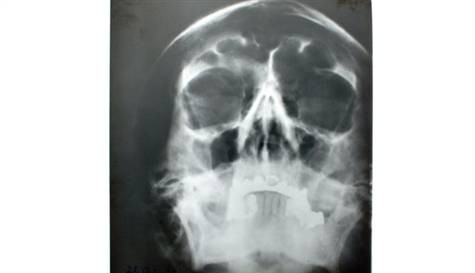

Adolf Hitler'in kafatasına ait X-ray 100 dolar fiyatla açık artırmaya çıkarılacak.

Abone olABD istihbaratı tarafından İkinci Dünya Savaşı'nın sona erdiği 1945 yılında hazırlanan raporda yer alan Adolf Hitler'e ait kafatası röntgeni, açık artırmada satılacak.

Hitler'in 6 doktorundan elde edilen belgelerle bir araya getirilen 47 sayfalık raporda, Hitler'in kafatasına ait 10 ayrı X-ray ile elektroenselogram bulunduğu belirtildi.

7x9 inç büyüklüğündeki kafatası röntgeni, ABD'deki Alexander Historical Auctions müzayede evinde satılacak.